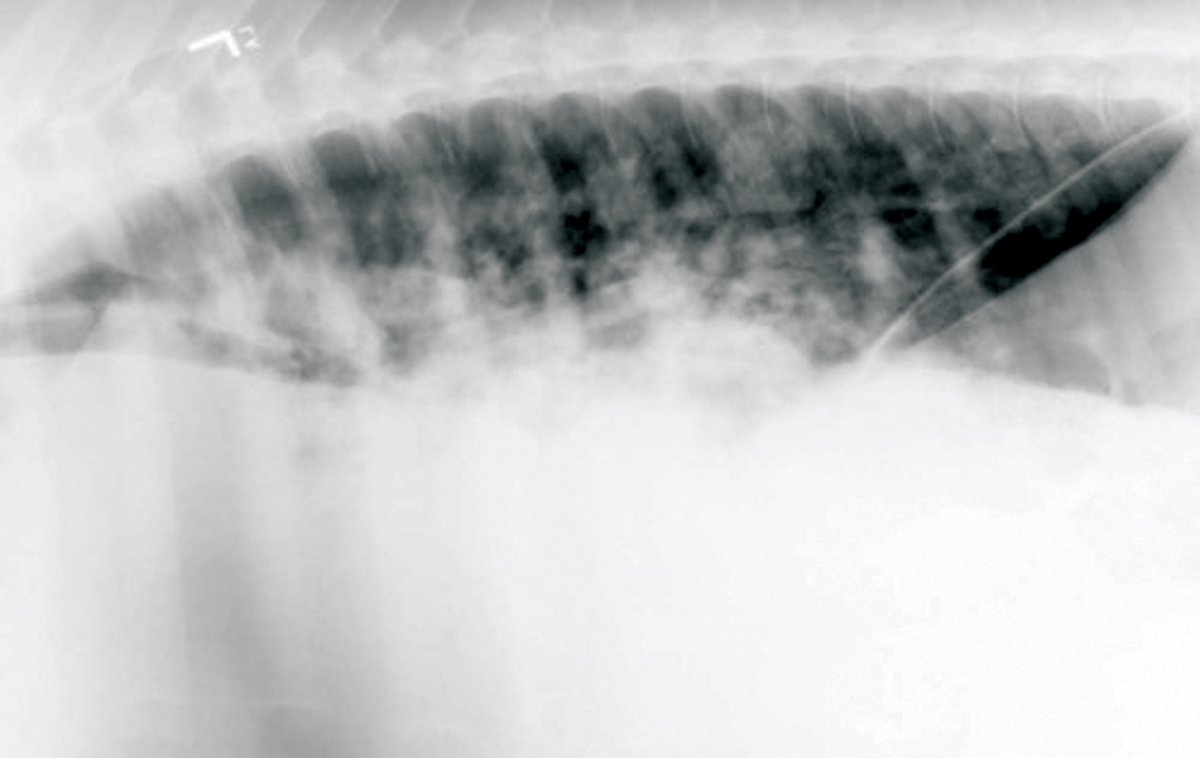

Update on Bacterial Pneumonia and Pleuropneumonia in the Adult Horse

Update on Bacterial Pneumonia and Pleuropneumonia in the Adult Horse Bacterial Infection In Horses Lungs A plaque of sternal edema is seen in horses with a large volume of pleural effusion. Foals develop pneumonia more commonly than adult horses. An infection of the lungs and the cavity between the lungs and underneath the chest wall (pleural space). Decreased or absent lung sounds in the ventral lung fields below the pleural effusion. They are more prone. Bacterial Infection In Horses Lungs.